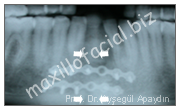

- Avulsed (knocked out) teeth (Figure 6,7)

Figure 6

Figure 7